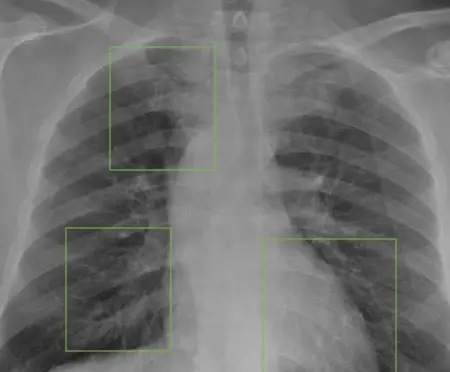

RIDE hợp tác với nhiều trường đại học trong nước để đào tạo và huy động đội ngũ sinh viên gắn nhãn chuyên môn hóa theo lĩnh vực, bảo đảm mỗi dự án đều có nhân sự am hiểu nội dung dữ liệu (ví dụ: sinh viên nông nghiệp gắn nhãn dữ liệu cây trồng, sinh viên y học gắn nhãn hình ảnh X-quang…).